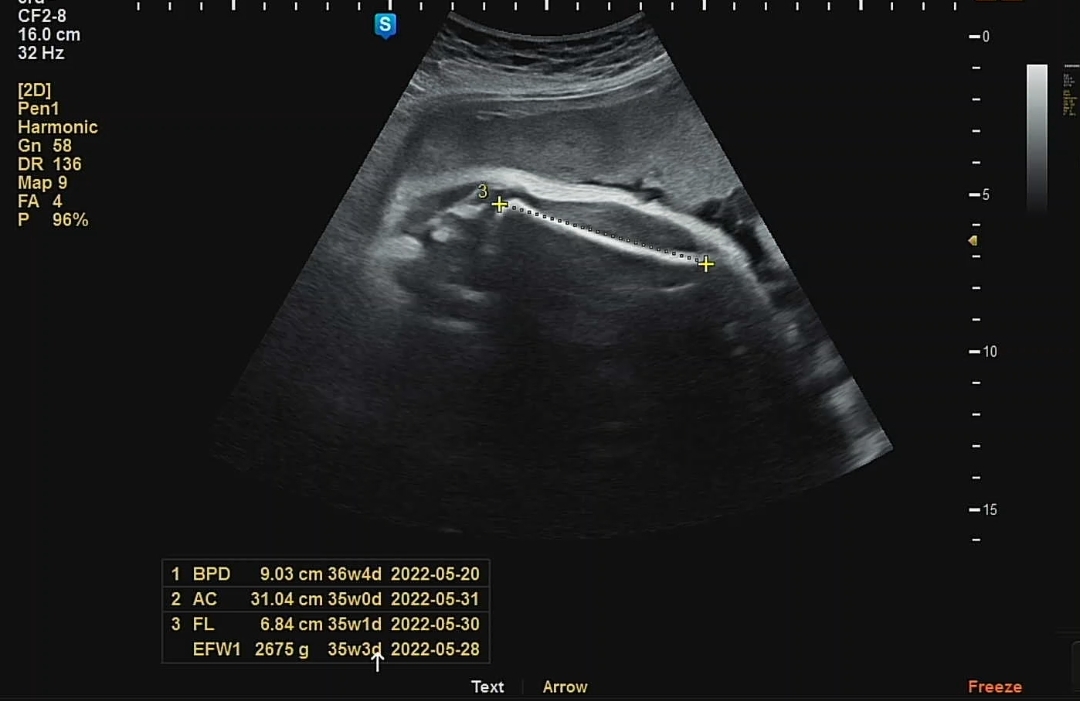

아내가 계속 신경썼던 것은 바로 체중! 2주 전에 검사했을 때 2227g이었는데 이번에는 2675g으로 총 448g이 쪘다. 이제껏 추이를 봤을 때 꽤나 많이 찐 편이었다.

저번 달이 비슷하게, 머리둘레(BPD)는 본 평균 주수대로 나왔으며, 배 둘레(AC), 다리 길이(FL)는 5일 차 정도 살짝 부족하게 나왔다. 그래도 크게 영향 있는 정도가 아니라니 다행.